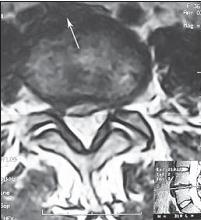

МРТ № 13

МРТ № 14

На МРТ № 13 наблюдается медиолатеральная грыжа межпозвонкового диска (заднебоковая)

На МРТ № 14 наблюдается фораминальная грыжа межпозвонкового диска с локализацией внутрь межпозвонкового отверстия